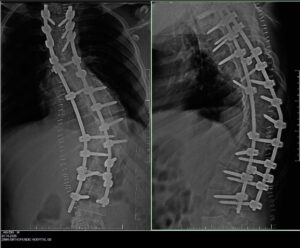

A multidisciplinary surgical team led by Prof. Dr. Fareed Ullah Khan Zimri has successfully completed a complex corrective spinal surgery on a 20-year-old male patient suffering from rigid kyphoscoliosis at ZIMRI Orthopedic Hospital in Islamabad. Alhamdulillah, the patient is now recovering well under close postoperative care and monitoring.

The successful outcome at ZIMRI Orthopedic Hospital highlights the importance of precision, coordination and modern intraoperative support in complex spinal surgery and marks a proud moment for Islamabad’s healthcare sector as it continues to expand advanced spinal and orthopaedic services locally.